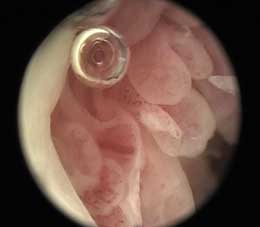

针刀镜技术是在无菌环境下,由专业操作医生,利用针刀镜操作设备及内窥镜,进行可视化操作。针刀镜治疗切口小于0.4厘米,在治疗过程中,专业操作医生利用通道可进行局部剥离、灌洗、注射、置药等多项操作。快速剥离和疏通关节及病变组织,解除粘连,消除炎症,恢复关节功能,以达到临床快速诊治风湿骨病的治疗目的。

针刀镜治疗切口极小, 多开通2个操作通道,在治疗过程中通过剥离和疏通关节和病变组织及关节腔灌洗,解除黏连,消除炎症,恢复功能。

微创治疗出血少,在治疗后12~24小时内,偶有沉重感和轻度疼痛,以后逐渐消失,24小时后即可进行功能恢复性活动。